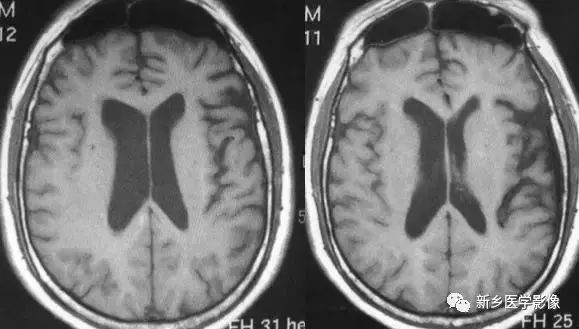

- Huntington's 病(亨廷顿舞蹈症):是一种常染色体显性遗传的、基底节和大脑皮层变性性疾病,主要损害基底节和大脑皮层,尾状核、壳核病变最明显。病理表现为:小神经节细胞严重破坏,大细胞也减少、尼氏体消失、核固缩、出现类淀粉小体,还有脱髓鞘改变和胶质增生,基底节部受累常最明显且发生最早。临床主要根据3大特征:舞蹈样动作、痴呆、家族史诊断。

- 帕金森病:是一种常见的锥体外系疾病。临床以震颤、肌强直和运动障碍为特征。静止性震颤通常为首发症状,休息和安静时明显。CT除有脑萎缩外,有时可见基底节钙化。MR T2WI上基底节区和脑白质内常有多发高信号斑点存在。